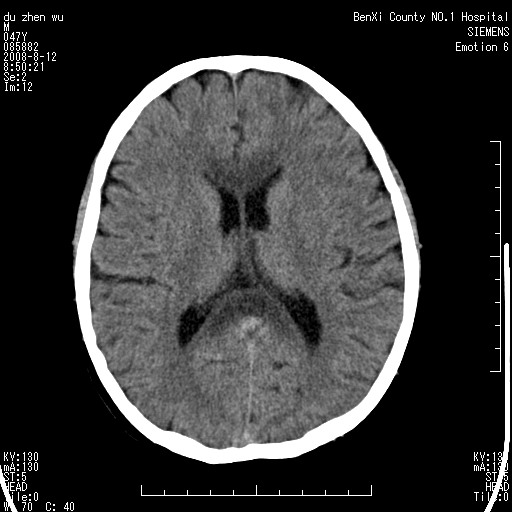

标题: CT15142:M47Y,胼胝体低密度病变 [打印本页]

标题: CT15142:M47Y,胼胝体低密度病变

男、时有神智不清,头晕,能正常回答问题,无肢体偏瘫

考虑胼胝体变性(脱髓鞘病变),找到一篇论文

典型,支持 胼胝体变性(脱髓鞘病变